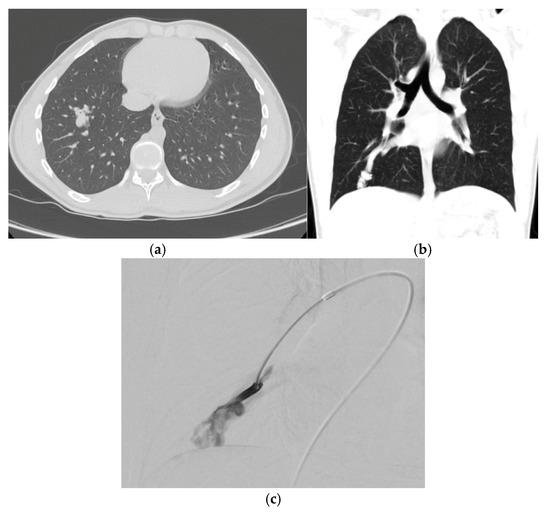

3.2. Computed Tomography (CT)

3.3. Angiography